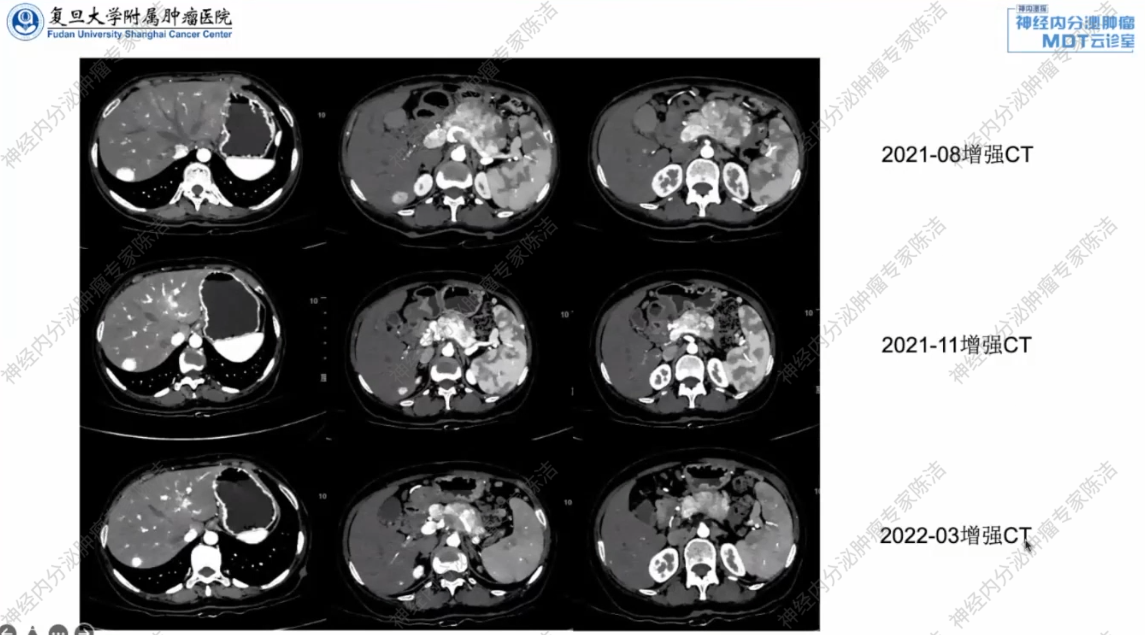

2021年8月,患者转至复旦大学附属肿瘤医院继续治疗。复查增强CT显示,胰体尾肿块,考虑MT,脾血管受累,门脉癌栓形成,SMV可疑受侵,肝多发转移,门脉海绵样变性。与外院2021年6月CT相比,疗效评估为部分缓解(PR)。

2021年11月,再次复查增强CT,病灶持续缩小,疗效评价仍为PR。

2022年3月,复查增强CT显示胰腺体尾部及肝转移病灶大小与前次相仿,部分病灶略有缩小,疗效评估为缩小的疾病稳定(SD)。

放射诊断科汤伟教授:本病例的系列CT影像动态、直观地记录了不同治疗方案下的疗效变化:索坦治疗初期稳定,后快速进展;而在换用CAPTEM化疗后,无论是胰腺原发灶还是肝转移灶,都带来了持续的肿瘤退缩。这一系列的影像变化为临床判断疗效、调整方案以及最终评估手术可能性提供了至关重要的客观依据。

胰腺外科徐晓武教授:患者初诊时,肿瘤体积巨大,且已侵犯门静脉、肠系膜上静脉等重要血管并形成癌栓,属于不可手术切除状态。经过CAPTEM方案有效的转化治疗后,肿瘤显著缩小,为手术切除创造了潜在的机会。建议在完成预定化疗周期后,再次进行详细的影像学评估,若条件允许,可积极考虑手术干预,以期达到根治或最大程度减瘤的目的。